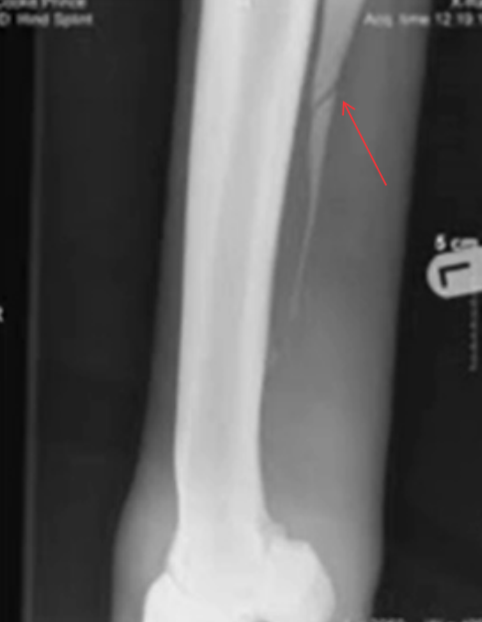

Fractuur van de radius en ulna van de hond

totale fractuur

Dwarse fractuur met een butterfly-fragment aan de laterale zijde